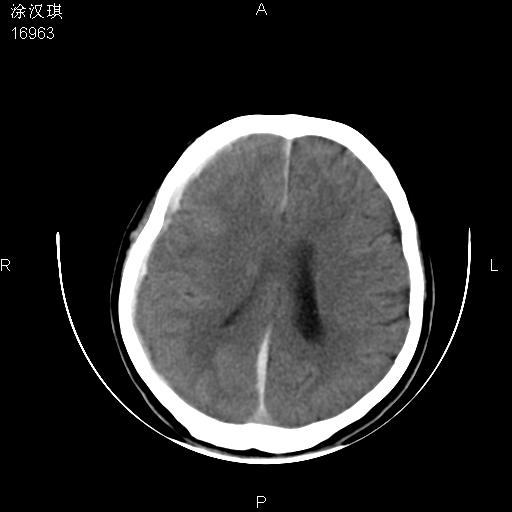

以下是引用chinazhouhua在2008-5-1 12:06:00的发言:[br]影像上来看,这是个典型的硬膜下血肿,包括右侧额颞部、大脑镰下、小脑幕下,而且在右侧额颞顶枕部、大脑镰下没看到高密度出血向脑沟内延伸,但是小脑幕下硬膜下有时候和蛛血不是很好鉴别,而且硬膜下很多时候伴有蛛血,往往在复查的时候出来,所以这种病人还是应该考虑硬膜下血肿伴有蛛血。

以下是引用zsl6918在2008-5-1 15:34:00的发言:[br]本病例主要表现为急性硬膜下血肿。